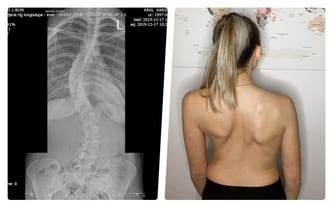

Moje plecy opowiadają historię bólu... Operacja ostatnią nadzieją!

Cel zbiórki: ASC - operacja skoliozy w Turcji

Skolioza